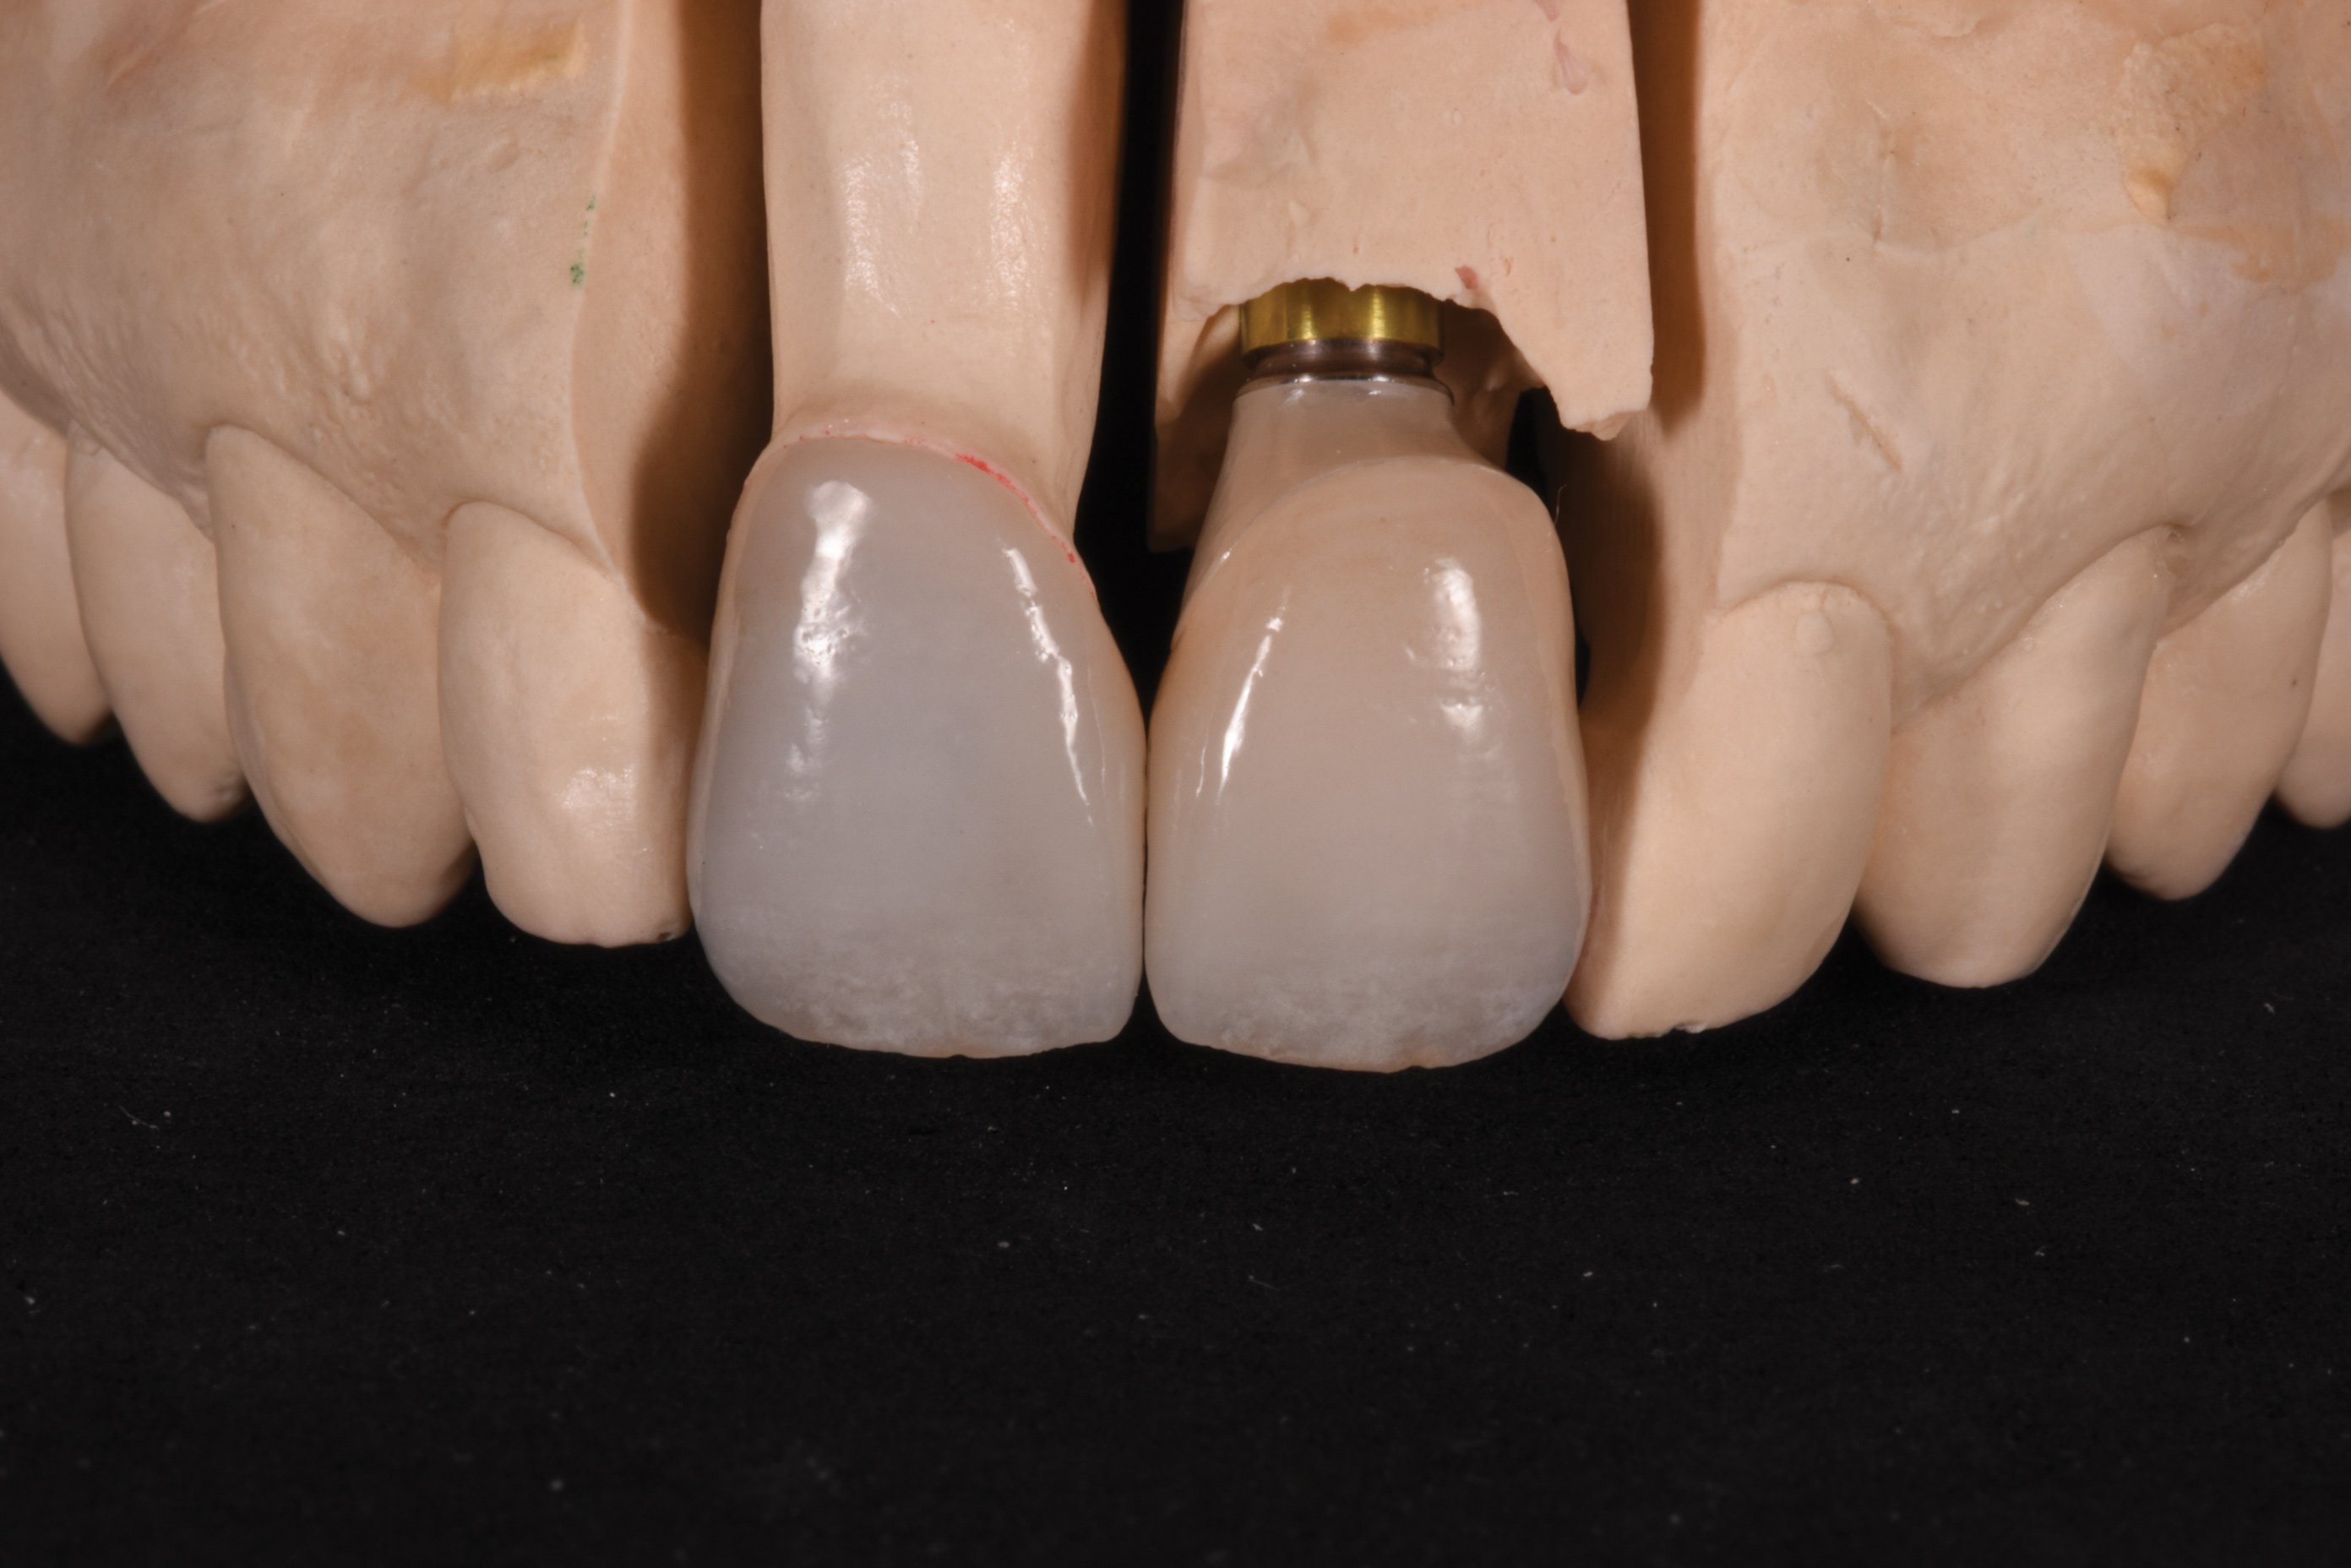

Fig 7. Labial view (laboratory) of wax pattern and copy milled zirconia substructure using angulated screw channel system.

Figure 7